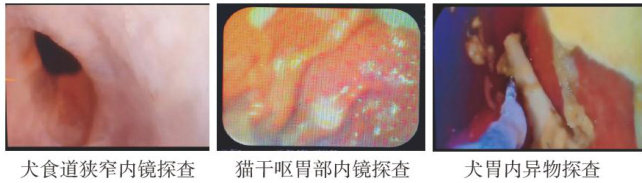

实践案例 | 兽用内窥镜在动物医院临床诊疗技术上的应用

实践案例 | 兽用内窥镜在动物医院临床诊疗技术上的应用